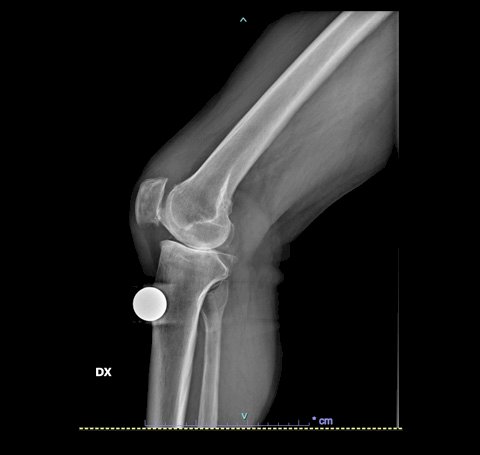

Una volta che l’ortopedico si è fatto un’idea delle funzionalità del ginocchio è necessario eseguire un primo esame diagnostico attraverso i Raggi X, al fine di valutare l'entità del danno presente. Alcuni casi spingono i chirurghi a richiedere anche un’indagine diagnostica più approfondita attraverso una risonanza magnetica, al fine di valutare le condizioni di cartilagine e legamenti.

In basso le lastre preoperatorie di un pz con gonartrosi mediale.